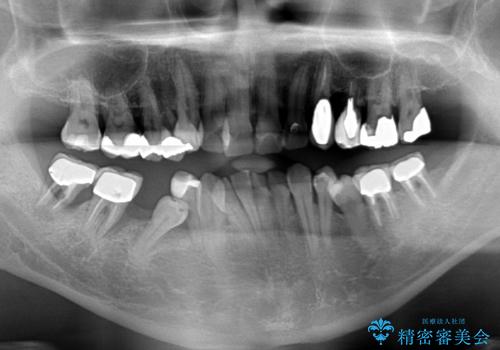

- 歯並びやグラグラする奥歯など、気になる所を全部治したいとのことで来院された患者様です。

奥歯は咬み合わせや歯周病により歯槽骨が失われていたり、むし歯や破折している歯などがあったりと、歯周病治療やインプラント補綴、矯正治療など、総合的に治療が必要と診断されました。

まずは歯周病治療やインプラント埋入を行い、環境が整った後にワイヤーを併用したインビザライン矯正を行い、オールセラミッククラウンにて補綴治療を行うこととしました。